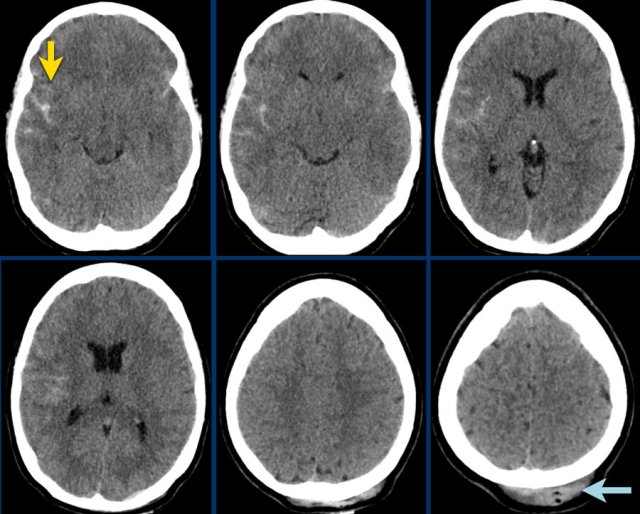

Isodense subdural hematoma

As a subdural hematoma ages, the density of the hematoma will decrease and may be the same as the density of the brain, which make it difficult to detect the hematoma.

Here a case of an isodense subdural hematoma which is very hard to detect (arrows).

Notice that on a higher level there is a bilateral subdural hematoma.

A subdural hematoma can spread along the falx and tentorium as seen in this case.

Subarachnoid hemorrhage

The images show hyperdense blood in the subarachnoid space of the Sylvian fissure (yellow arrow).

Notice the subgaleal hemorrhage in the right occipital region (blue arrow).

This is a coupe contrecoupe type of injury.

This is another coupe contrecoupe type of injury with contusional hemorrhages and a subdural hematoma in the left frontal lobe near the skull base (red arrow).

There is a subarachnoid hemorrhage on the right with a fracture of the parietal bone (yellow arrow).